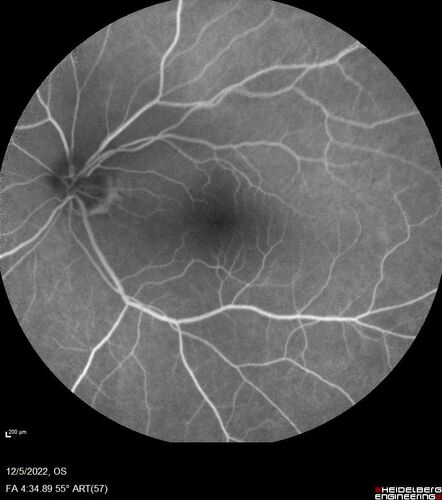

Macular schisis with no leakage on FA - Presumed Nerve pit maculopathy

73-year old female. Had treatment trial with Eylea with no benefit (4 months). Vision is 20/32 in left eye and has remained there (with a dense cataract).